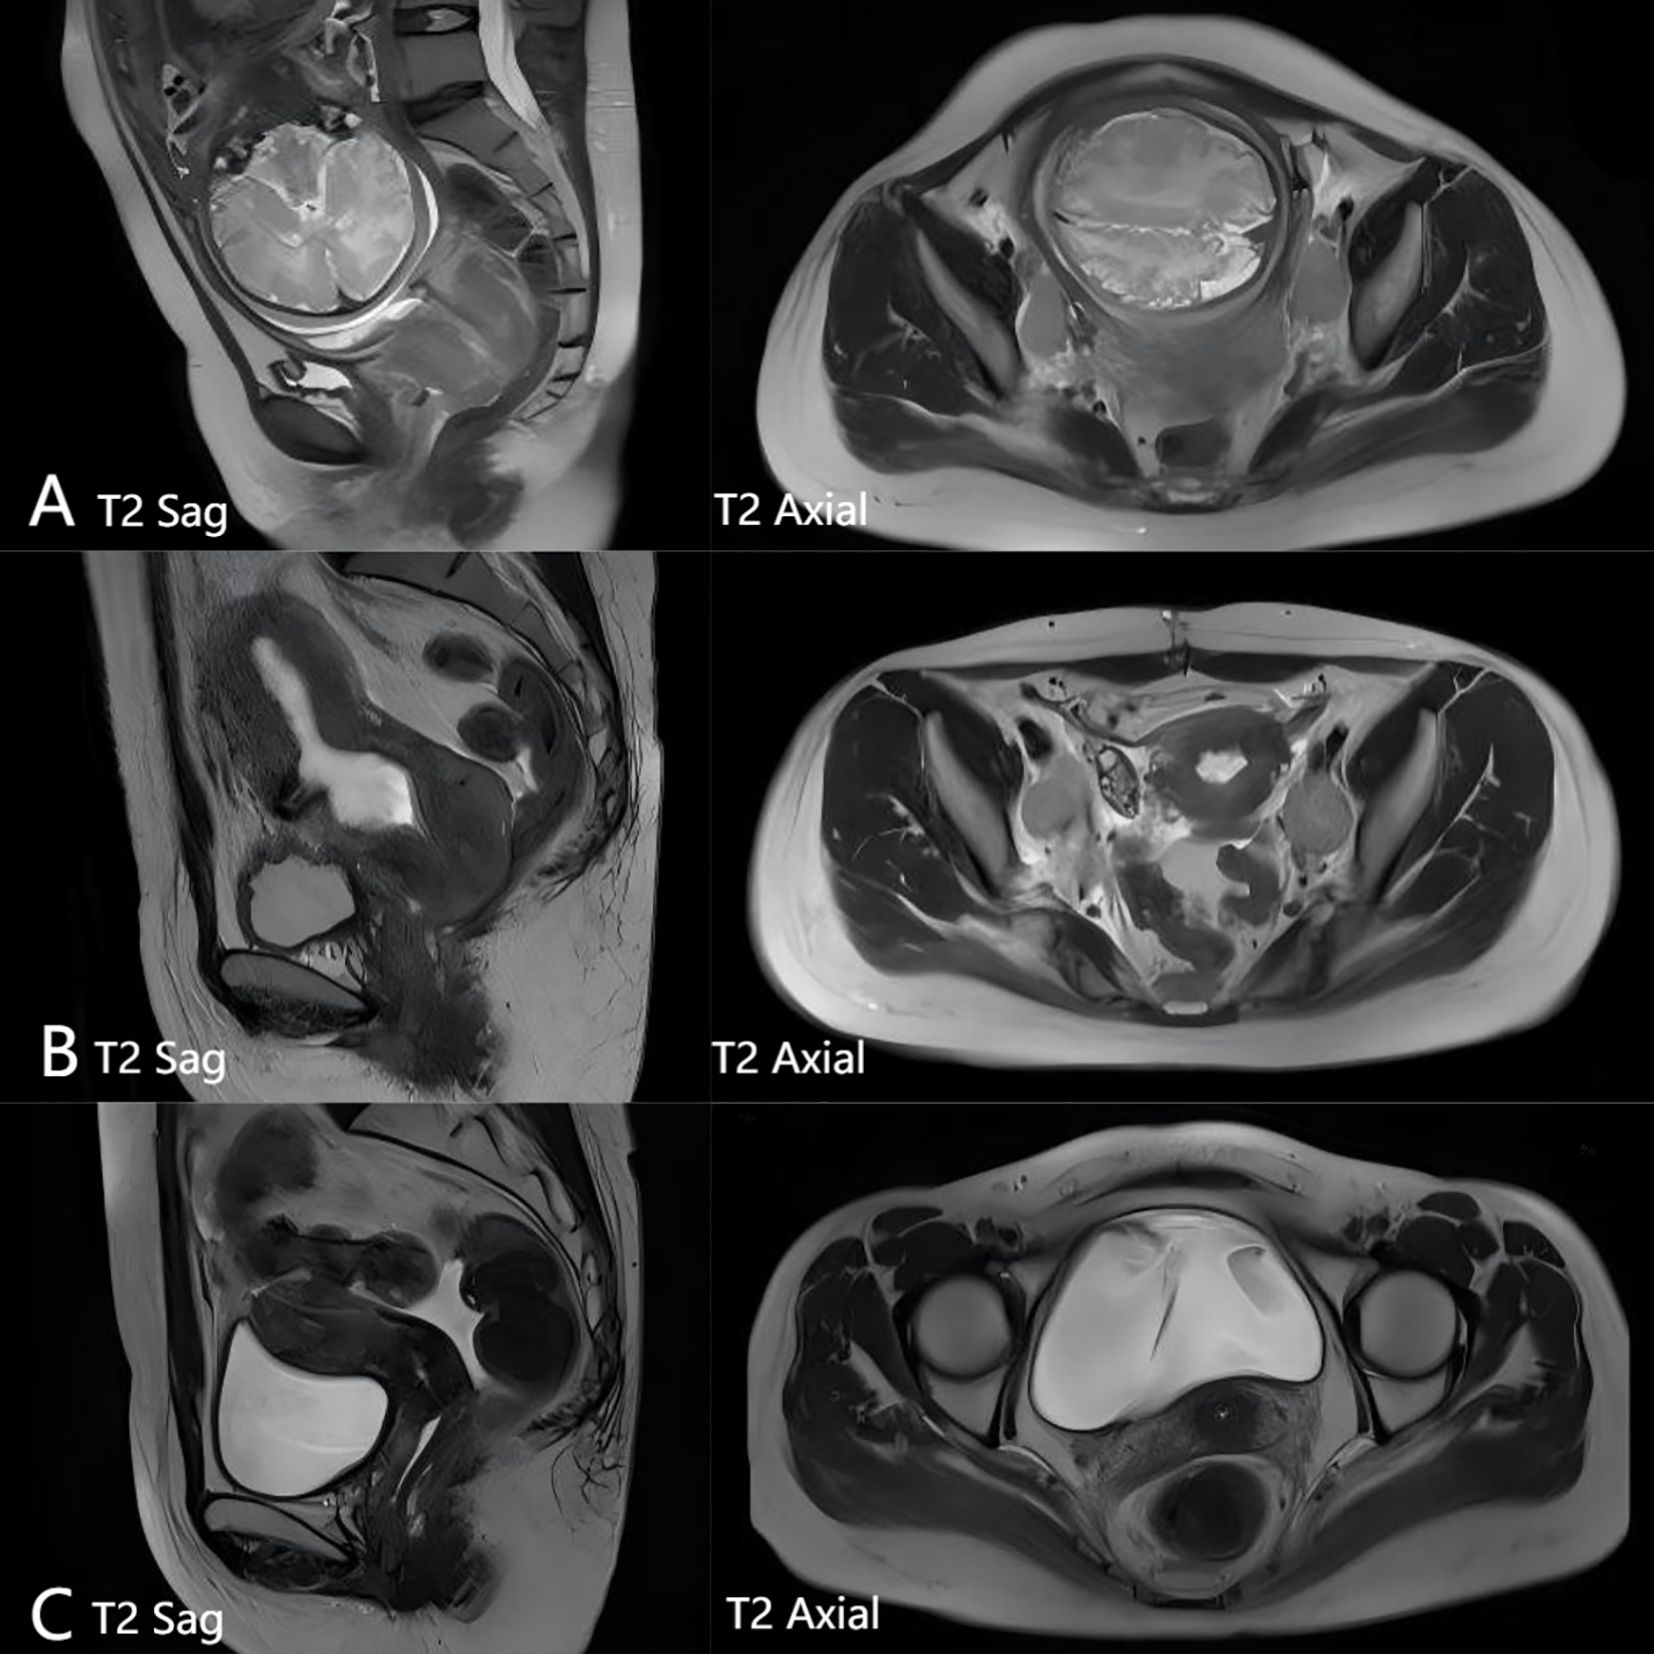

This article reports an extremely rare case of a 31-year-old pregnant woman diagnosed with large cell neuroendocrine carcinoma (LCNEC) of the cervix complicated by syndrome of inappropriate antidiuretic hormone secretion (SIADH). Admitted at 35⁺ ¹ weeks gestation due to vaginal bleeding, she was diagnosed with cervical LCNEC and pelvic lymph node metastasis. Following cesarean delivery, she developed severe hyponatremia (as low as 92 mmol/L) leading to coma during chemotherapy, meeting the criteria for SIADH. The hyponatremia was successfully corrected with the selective vasopressin V2 receptor antagonist tolvaptan. The patient subsequently achieved complete remission (CR) after concurrent chemoradiotherapy. However, the disease recurred with multiple metastases six months later. Despite multiple lines of therapy, she succumbed to multiple organ failure 19 months after initial diagnosis. This case highlights the highly aggressive nature and poor prognosis of LCNEC complicated by SIADH during pregnancy. Tolvaptan proved effective for the associated refractory hyponatremia but required careful monitoring to avoid sodium overcorrection. Dynamic serum sodium monitoring may serve as a potential biomarker for tumor recurrence. A review identified deficiencies in the management, including initial insufficient investigation into the cause of hyponatremia, aggressive fluid therapy exacerbating the condition, and delays in multidisciplinary collaboration and systemic therapy. This case underscores the critical importance of multidisciplinary collaboration and early, aggressive systemic treatment in managing such complex and rare malignancies.